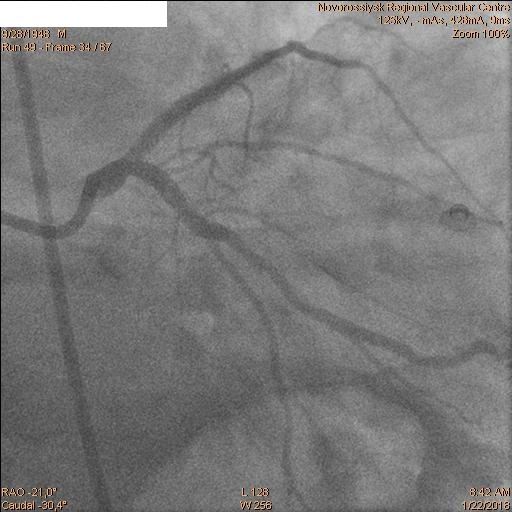

Затем последовательно перепроведены коронарные проводники в дистальные сегмента ПНА и ОА. Баллоном 2.5х20 мм выполнена предилатация ячеек стента. Далее выполнено стентирование ствола ЛКА с переходом на проксимальный сегмент ОА стентом 4.0х28 мм. Затем баллонами 2.5х20 мм и 2.5х15 мм выполнена «kissing» дилатация ствола ЛКА, устья ПНА и устья ОА с великолепным ангиографическим результатом.

Пациент переведен в ПИТ отделения неотложной кардиологии. ЭКГ после операции.